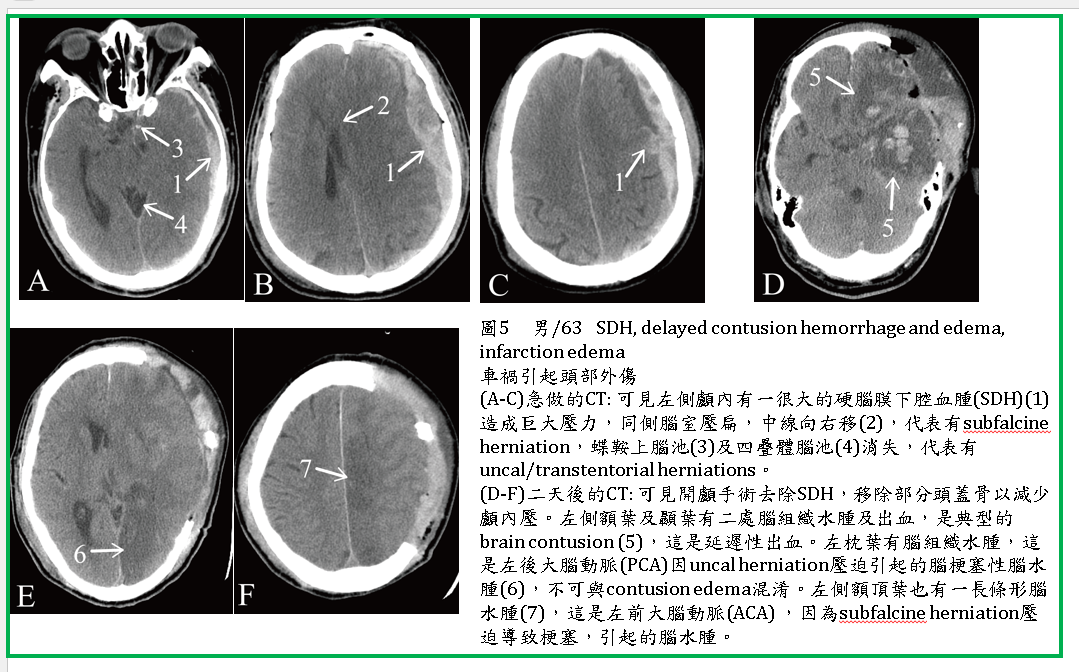

2. 腦挫傷常常合併SDH、EDH(圖1),也常合併SAH (圖3,4,5,6)、IVH 。

3. 有時,腦挫傷出血與EDH或SDH同時發生,EDH或SDH之腫塊效應較強,腦挫傷出血被壓住而出血較少。當EDH或SDH被手術移除後,顱內壓力變小,挫傷性腦出血反而會擴大,稱減壓後出血(decompression bleeding) (圖5) 。

是最常見的類型,在撞擊受傷的區域有不規則的腦水腫及多個點狀,或小塊狀出血。有些只有一個區域contusion (圖3) ,有些則多處(圖1,2,4,5)。